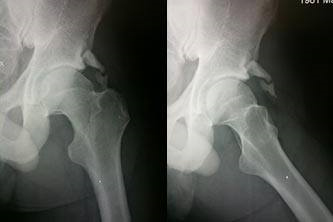

Prior to Resection of the Impingement Lesion

After Arthroscopic Impingement Resection